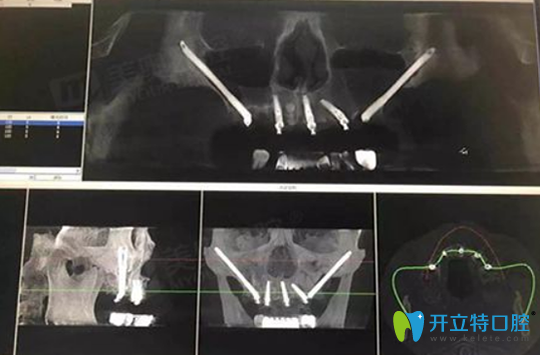

3月11日,周先生慕名來(lái)到杭州美奧口腔做全面檢查,CBCT口腔拍片顯示上頜余牙三度松動(dòng),右下頜4號(hào)牙與右下頜7號(hào)牙缺失。

患者周先生CBCT口腔影像:

患者周先生CBCT口腔影像